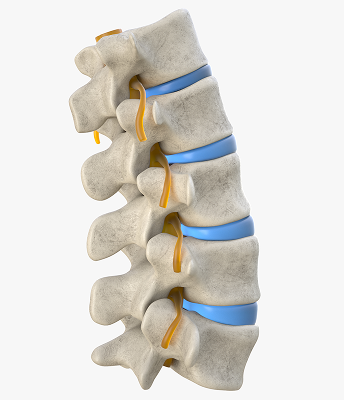

Abordaje en dolor discogénico, síndrome facetario, hernias discales y dolor radicular